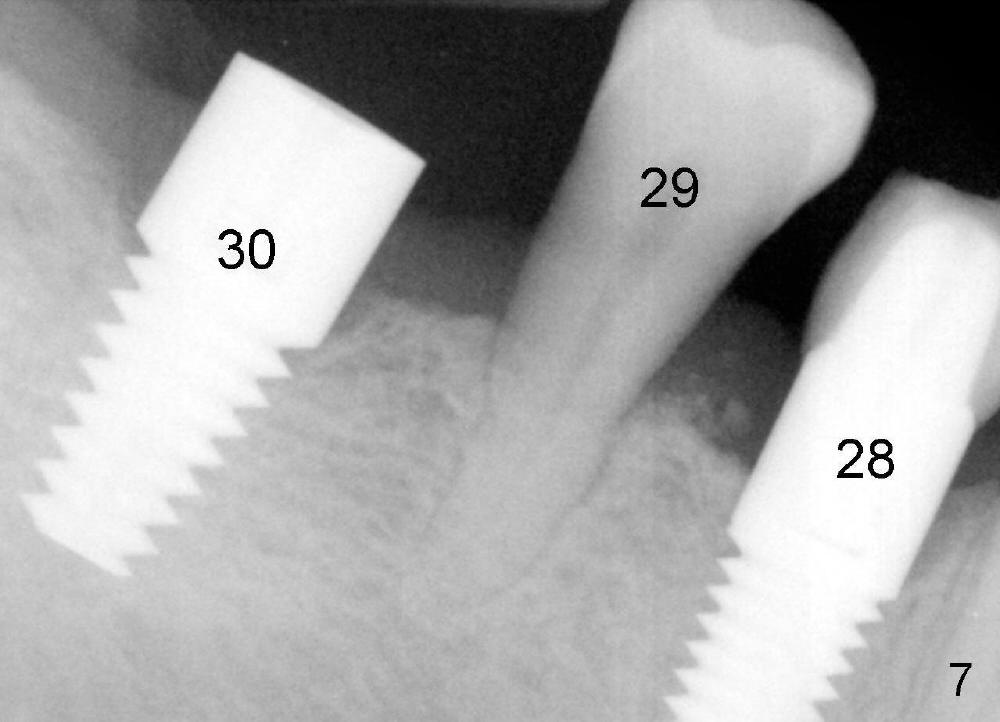

The patient returns for orthodontic treatment 7-8 months post implantation at the sites of #3, 20, 21, and 30 (Fig.4,6,7). He is willing to let the tooth #5 be extracted if necessary, since it has mobility. The tooth is only the functioning posterior tooth in his mouth (Fig.1). It must have occlusal overloading, particularly opposing the implant tooth #28 (Fig.1,7). Multiple implants and ortho treatment appear to be needed.